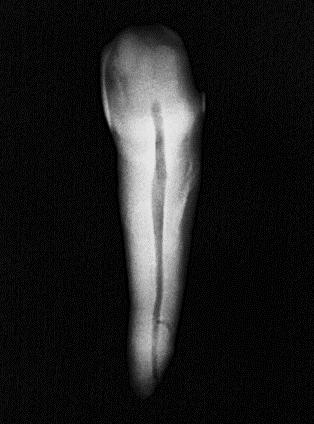

Se utilizaron 46 dientes extraídos unirradiculares superiores e inferiores con caries, pero sin compromiso radicular: sin ápices abiertos Los dientes con reabsorción radicular, fractura apical, caries que comprometieralaraízyápicesabiertosfueron descartados. Cada diente fue sometido a un proceso de limpieza por medio de ultrasonido para la remoción de cálculo y restos de tejido periodontal. Se le asigno un número a cada dienteysetomóunafotografíainicial(Figura 1).

Revista Espacio Universitario. Año 4. No. 9. Octubre 2022 17

Figura 1

FotografíainicialdeOD#27

Fuente: Pérez V, Salinas L. 2022.

Conductometría aparente

Es una de las etapas para obtener una medida de longitud, mediante una radiografía dentoalveolar, que corresponde a la distancia desde el punto de referencia coronal hasta el ápice radiográfico, definido como la porción

más apical del diente en una radiografía.

(Figura 2)

Figura 2

Conductimetría aparentedeOD#27

Fuente: Pérez V, Salinas L. 2022